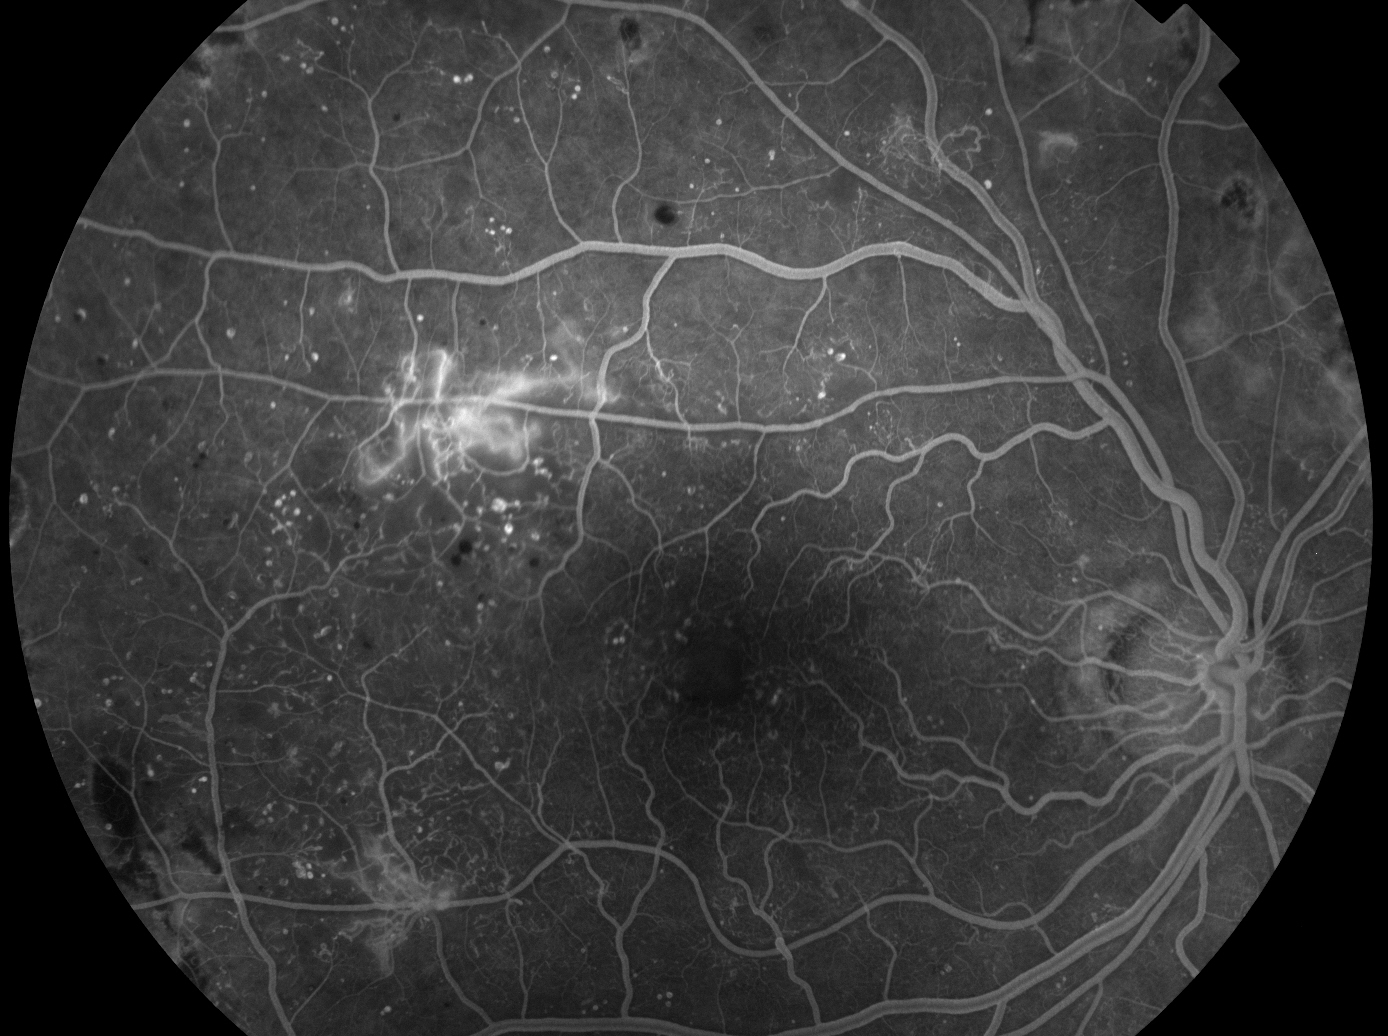

Retinopatia Diabetica

Occlusioni Vascolari Retiniche